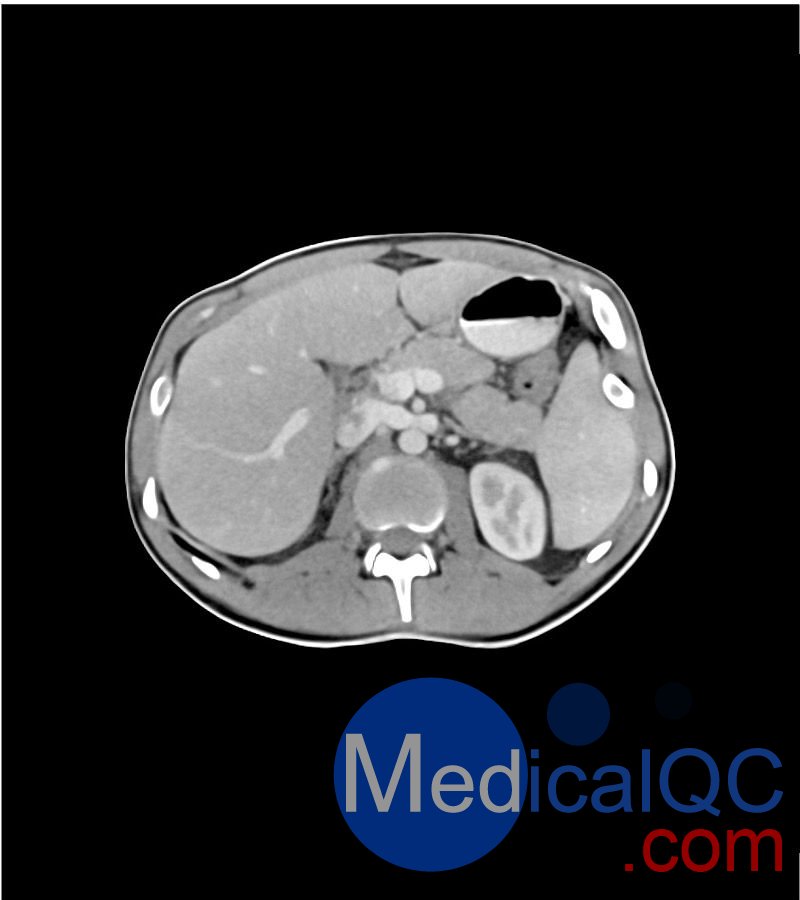

WEK-5501男性腹部模體,WEK-5501男性骨盤模體可模擬門靜脈期的腹部和盆腔增強掃描效果,掃描范圍覆蓋第一腰椎至?xí)巺^(qū)域。

該體模右側(cè)設(shè)有髂淋巴結(jié)腫塊(模擬病灶)。

1. 可對脈管系統(tǒng)、骨骼及軟組織進行逼真模擬,涵蓋的器官包括肝臟、膽囊、胰腺、脾臟、腎上腺、腎臟、胃、小腸、結(jié)腸、膀胱及前列腺。

2. 右側(cè)設(shè)有髂外淋巴結(jié)腫塊(模擬病灶)。

WEK-5501男性腹部模體,WEK-5501男性骨盤模體成像效果圖: